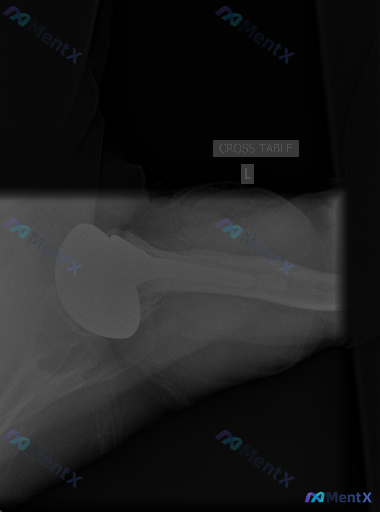

这张左肩关节置换术后X光片,你能看出异常吗?

整理到一份影像资料:左侧肩关节置换术后的腋位(Cross-table)X光片。

- 人工肱骨头假体及柄部位置良好,未见明显松动、断裂或透亮带

- 盂肱关节对位正常,无脱位/半脱位

- 假体周围骨质密度均匀,未见溶骨性破坏或明显骨赘

- 周围软组织轮廓基本正常,无明显钙化

影像报告给出的直接结论是“未见明显影像学急性异常”。